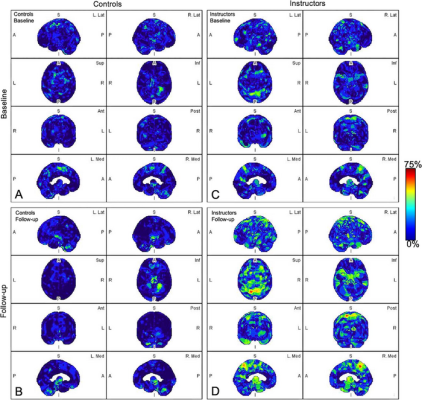

Parametric maps of amyloid deposition in healthy control participants (A and B) and blast-exposed military instructors (C and D) at baseline (A and C) and follow-up (B and D). The blue-to-red scale indicates the frequency of statistically abnormal amyloid uptake in a particular brain voxel. Whereas no abnormal amyloid uptake was identified at baseline or follow-up in healthy control participants (A, B), amyloid deposition occurred most frequently in blast-exposed participants in the superior parietal lobules, precuneus, cingulum, paracentral lobules, and anterior temporal and occipital lobes (D). A = anterior, Ant = anterior, I = inferior, Inf = inferior, L = left, Lat = lateral, Med = medial, P = posterior, Post = posterior, R = right, S = superior, Sup = superior. Image courtesy of RSNA.

Abnormal amyloid accumulation was seen in six of the nine participants who were exposed to explosions. Three of the participants had one region of the brain with increased amyloid accumulation, two participants had two regions, and one participant had three regions with abnormal accumulation.

None of the healthy control participants showed any abnormal amyloid accumulation.